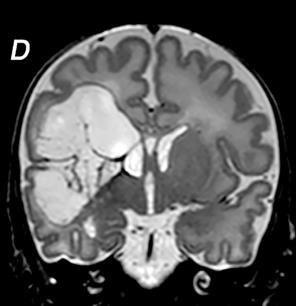

Germinal matrix-intraventricular haemorrhage (GMH-IVH)

Focal infarction

White matter injury

Global injury from hypoxic-ischaemic encephalopathy (HIE)